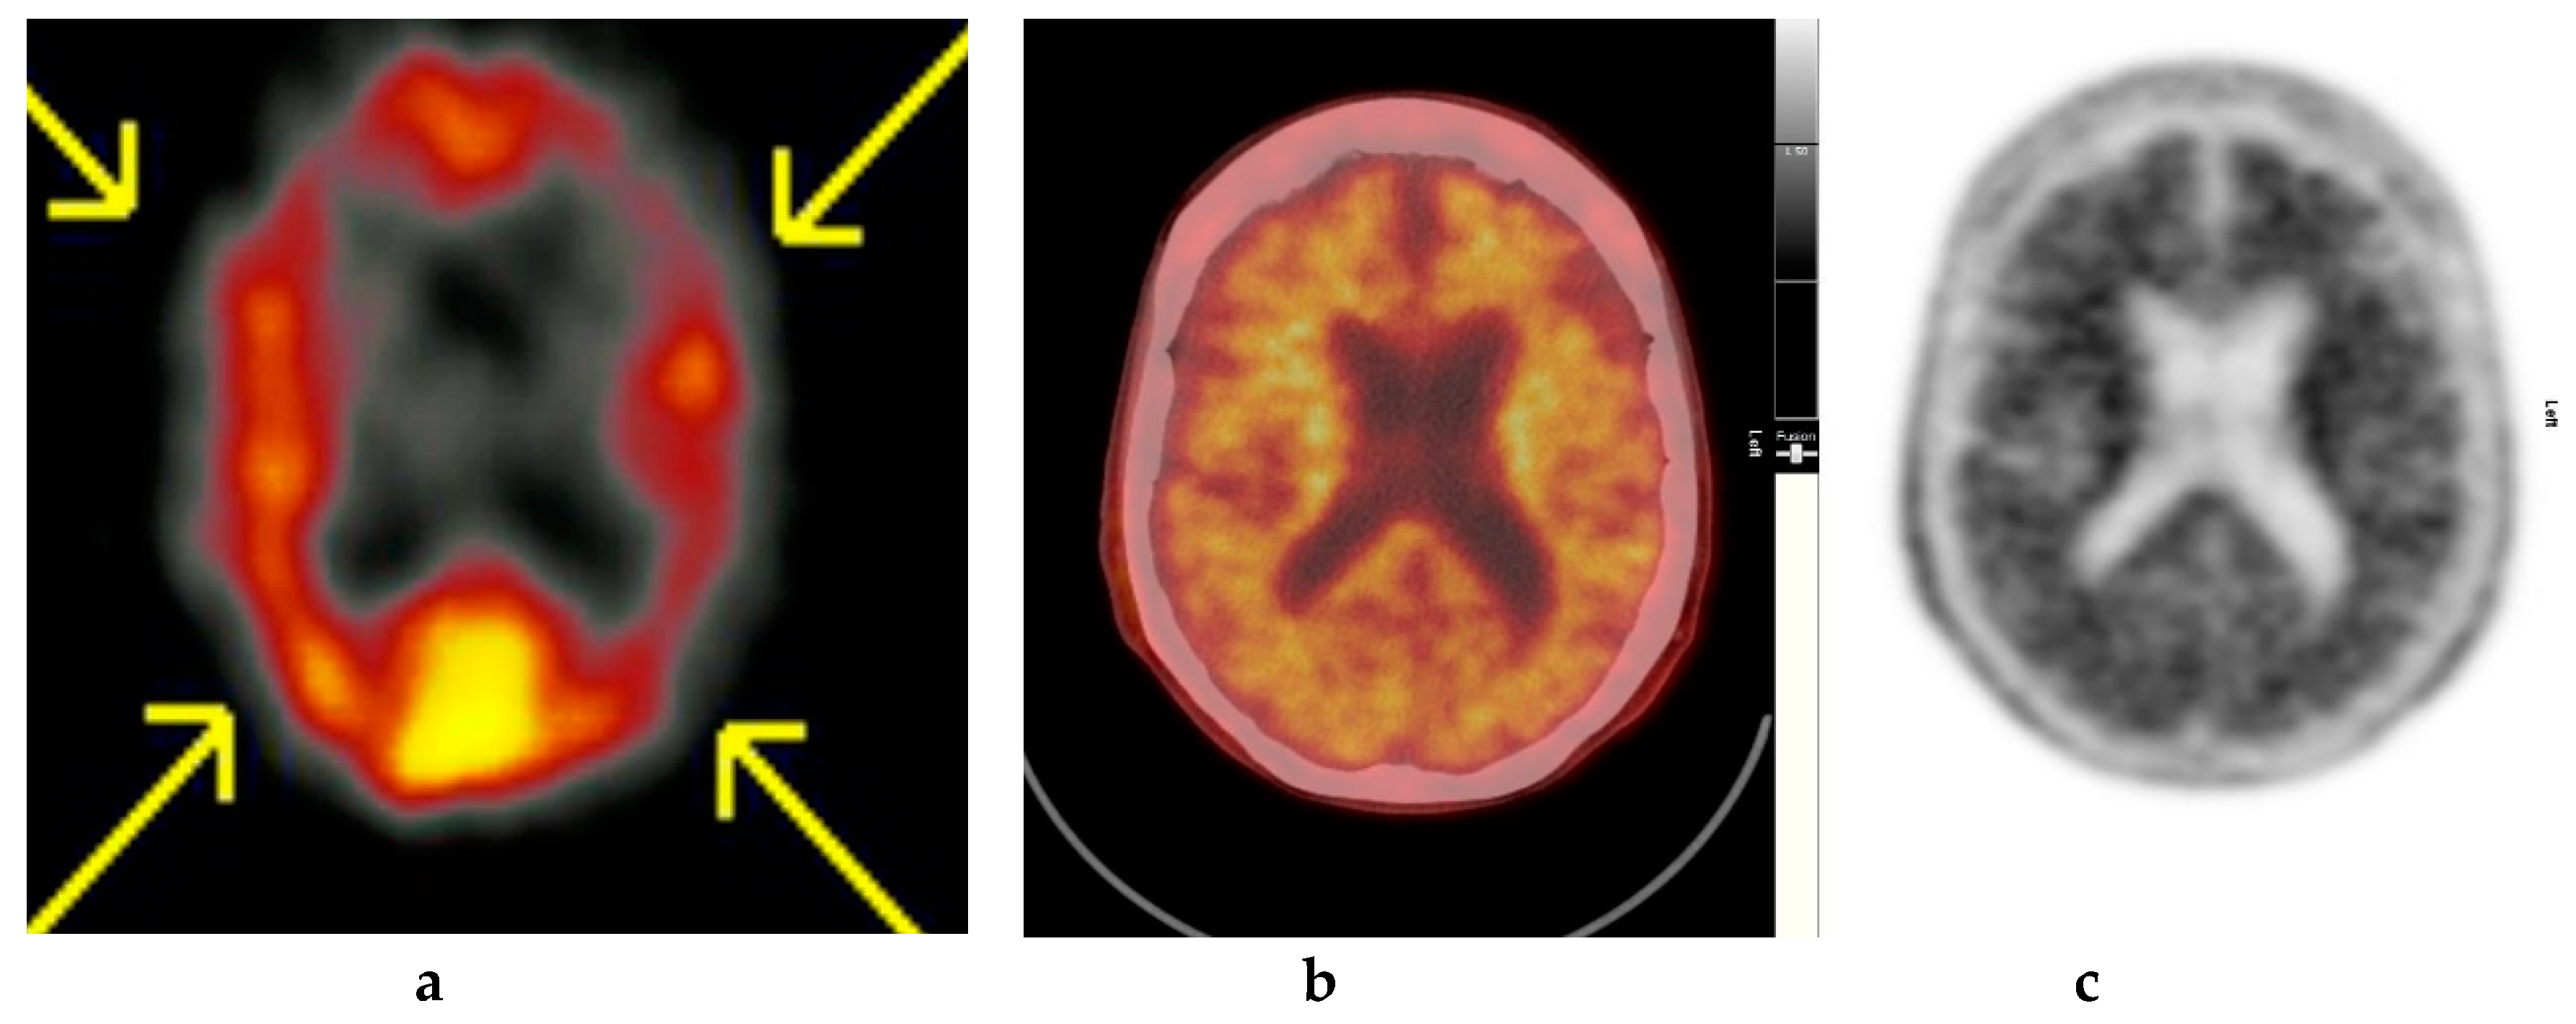

Figure 3.

Abnormal study. Seventy-four year old male patient with a history of short term memory problems/gradual memory decline for some time and a query of dementing pathology. (a) and (b) [18F]FBP shows loss of contrast between grey and white matter in all sections of the brain. The scan is suggestive of beta-amyloid plaque deposition and in a patient with the above clinical presentation is suggestive of early AD. (c) MRI brain scan (multiplanar and multi sequence acquisitions) with some motion artefact shows generalised age appropriate cerebral atrophy, proportionate symmetrical temporal lobe atrophy, and corresponding dilatation of the cerebrospinal fluid (CSF) spaces. Moderate to marked periventricular T2 white matter hyperintensities likely to represent chronic small vessel ischemic changes. No diffusion restriction or space occupying lesions were identified. (Figures are courtesy RLBUHT Hospital database.).